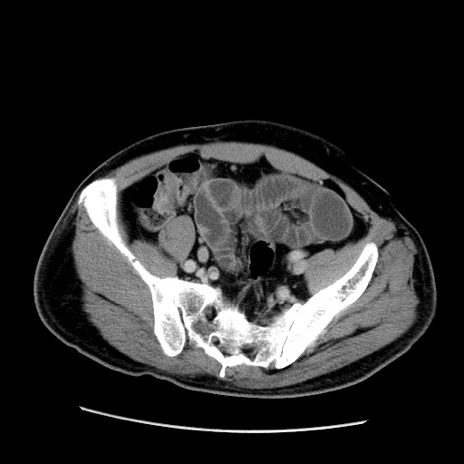

症例22(横断像)

【症例】50歳代男性

【主訴】腹痛

【現病歴】AVMからの被殻出血のため回復期リハ病棟入院中。 本日午後3時頃急に下腹部痛が出現した。

【既往歴】AVM、被殻出血、虫垂炎、高血圧

【身体所見】意識晴明、左半身不全麻痺、会話の理解は良好、36.5°C、腹部:膨隆、全体に板状硬、下腹部正中に圧痛点あり、反跳痛-、筋性防御不明、右下腹部にope scar

【データ】WBC 9400、CRP 0.06